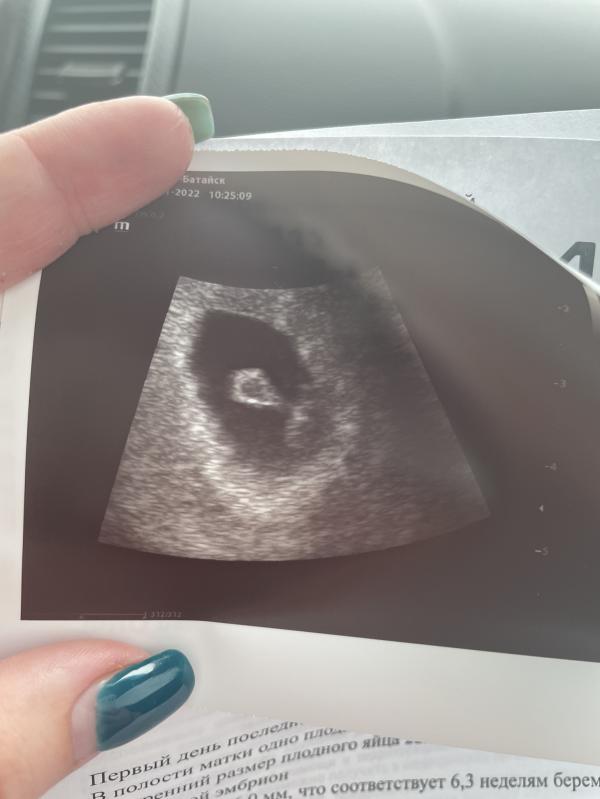

УЗИ на сроке 6 недель и 4 дня: бьющееся сердечко 134 удара, как дела?

УЗИ в 6н4д. Уже хорошо подросли, и сердечко слышно, 134уд. ❤️